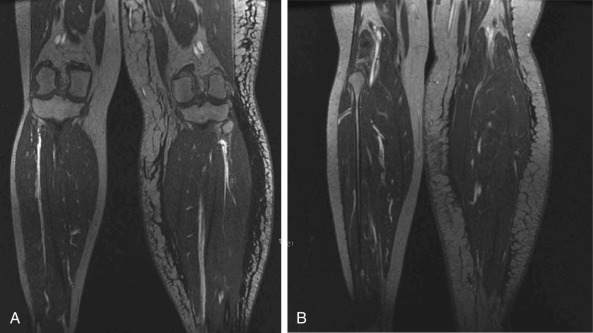

Radiographic imaging includes magnetic resonance angiography (MRA) of both the recipient and potential donor sites. Ablavar contrast, as opposed to gadolinium, is used and stays in the blood for a longer period of time yielding higher resolution. The thin-cut venous phase is used for review. For the recipient site , the fluid versus fat component as well as limb volume can be calculated ( Fig. 8.4 ). Occult recurrence and severe stenosis of the axillary, femoral, or iliac veins following surgery and radiotherapy can also be visualized. If present, venography can better characterize the nature of vein stenosis. We have seen a number of patients with axillary node dissection and radiation with severe axillary vein stenosis requiring extensive lysis to dilate the vein and one patient who required axillary vein reconstruction. As stated earlier, venous hypertension can be a component of limb swelling and could compromise the VLNT or LVA. MRA of the recipient site is performed 1 year postoperatively to confirm viability and quantity of lymph nodes successfully transferred.